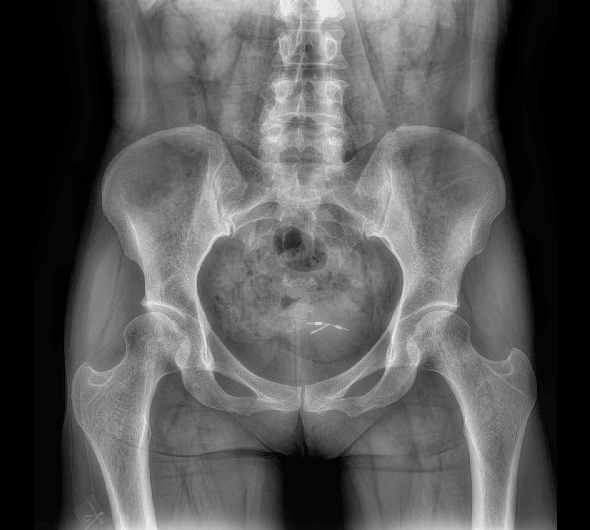

臨床圖像